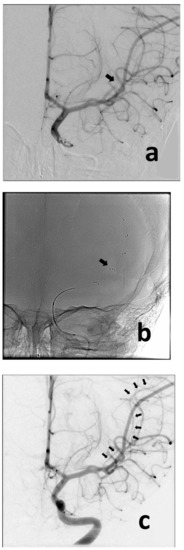

A previously healthy 3-year-old boy was admitted to the University of Missouri Columbia Children’s Hospital on 16 December 2020, with a 4-day history of acute gastrointestinal symptoms (i.e., nausea, vomiting, abdominal pain), fever, rash, shock, mild left ventricular myocardial dysfunction, elevated inflammatory markers (C-reactive protein, procalcitonin, ferritin, transaminases, interleukin-1, interleukin-6), and evidence of COVID-19 (RT-PCR, antigen test, serology positive) (Table 1), thereby satisfying the criteria of MIS-C [1,3,4,5,6]. He was rapidly treated with intravenous methylprednisolone (2 mg/kg/day, divided every 6 h), intravenous immunoglobulin (2 g/kg), enteral aspirin (81 mg per day), and prophylactic subcutaneous low-molecular-weight heparinoid (0.5 mg/kg twice daily). On the second inpatient day, he developed sudden weakness in the right arm and leg, aphasia, and an overall neurologic deficit that amounted to a Pediatric National Institutes Stroke Scale (PedNIHSS) score of 26. Magnetic resonance imaging (MRI) showed evidence of restricted diffusion consistent with ischemia of the territory of the middle division of the left middle cerebral artery—LMCA (md)—(Figure 1a), and yet, minimally increased signal of the analogous volume of tissue in the Flow Attenuation Inversion Recovery (FLAIR) sequence (Figure 1b). In addition, magnetic resonance angiography (MRA) demonstrated occlusion of the LMCA (md) (Figure 1c), leading to the decision to proceed with urgent thrombectomy. Cerebral angiography confirmed the expected occluded artery (Figure 2a), which was successfully recanalized by retriever thrombectomy (Figure 2b,c). Successful reperfusion [Thrombolysis in Cerebral Infarction (TICI) = 2b] of the affected vascular territory was immediately confirmed via digital parenchymography (Figure 3). Over the 12–24 h following the procedure, the child regained spontaneous movement of his right arm and leg and began to communicate verbally (PedNIHSS = 10). He continued to progressively improve, reaching near-normal motor and language function (PedNIHSS = 5) at hospital discharge one week later, and displayed no neurologic deficits at 30 days in the outpatient clinic. Additional imaging studies, including echocardiography and venous Doppler ultrasound of all limbs, proved unremarkable. However, he was found to be heterozygous for Factor V Leiden mutation.

Figure 2. Anteroposterior angiographic and fluoroscopic views of the thrombectomy procedure. Baseline image confirms occlusion of the MCA (md) (a) (black arrow). The retriever was deployed across the point of occlusion (i.e., normal-to-normal) (b) (black arrow). Following removal of the retriever, the MCA (md) is now visualized (c) (multiple black arrows), despite showing some spasm (typically caused by the device).